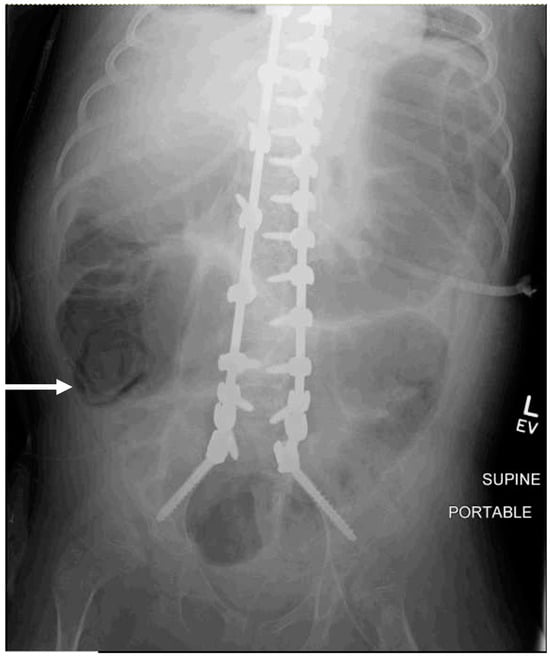

Two of thirty patients (6.7%) had notable KUB findings. One patient with a history of chronic constipation had an incidental finding of fecal impaction for which the gastroenterology team was consulted, and a bowel cleanout regimen including daily enemas was initiated prior to discharge. The other KUB study reported a concern for pneumatosis of the colon [Figure 1]. Pediatric surgery was consulted and, as this could not be excluded, the patient underwent an exploratory laparotomy due to a concern for bowel ischemia and/or perforation. The intraoperative evaluation did not show any concerning findings and the abdomen was closed primarily and treated as an ileus. Overall, twenty-nine (96.7%) of the thirty patients had postoperative abdominal radiographs performed that resulted in no significant change in management. Furthermore, in the case that the patient had a surgery performed, the findings were unremarkable.

Diagnostic tests with poor specificity risk false positive findings. In this study, one patient with a history of gastrostomy tube dependence, tracheostomy, and severe developmental delay received a KUB that reported colonic pneumatosis. This nonspecific finding can present with bowel obstruction as well as postoperative ileus. Ultimately, the patient underwent an exploratory laparotomy with pediatric surgery, and there was no evidence of bowel ischemia or obstruction at the time of surgery. The patient was treated with 7 days of bowel rest and prophylactic antibiotics, after which repeat abdominal radiographs demonstrated the resolution of pneumatosis, and feeds were restarted via the patient’s gastrostomy tube without further complication. An initial treatment of ileus without additional radiographs could have led to the same clinical result and avoided an unnecessary surgical procedure.

Figure 1. A supine AP abdominal radiograph of a nine-year-old male who underwent PSF for neuromuscular scoliosis was performed for worsening abdominal distension on postoperative day #2. The white arrow demonstrates the area concerning for possible pneumatosis coli, or free air within the wall of the colon.